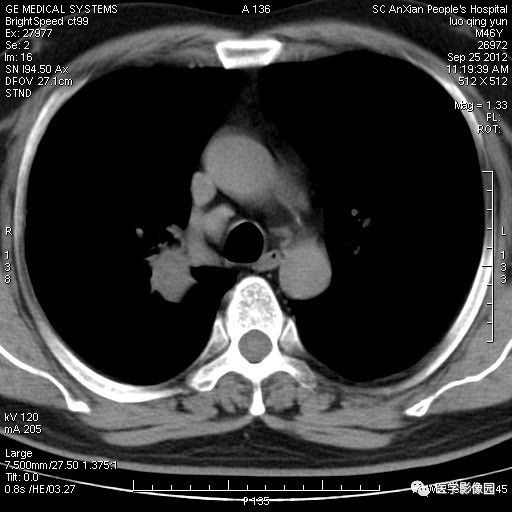

影像学表现:右上肺见不规则团块状高密度阴影,略有分叶级毛刺,边缘模糊,邻近胸膜增厚,增强扫描呈轻中度强化。

诊断结果:右上肺炎性假瘤

本病影像学表现无绝对特征性。单发多见,多位于肺表浅部位,多呈圆形或椭圆形,直径多在2-5cm或更大;多有假包膜,边缘多清晰光整,有时也毛糙,并可有分叶或毛刺;邻近胸膜局限性增厚、牵拉,病灶边缘呈桃尖样突起即桃尖征(尖端指向胸膜);增强扫描多呈中度均匀强化,持续时间较长。亦可显著强化。